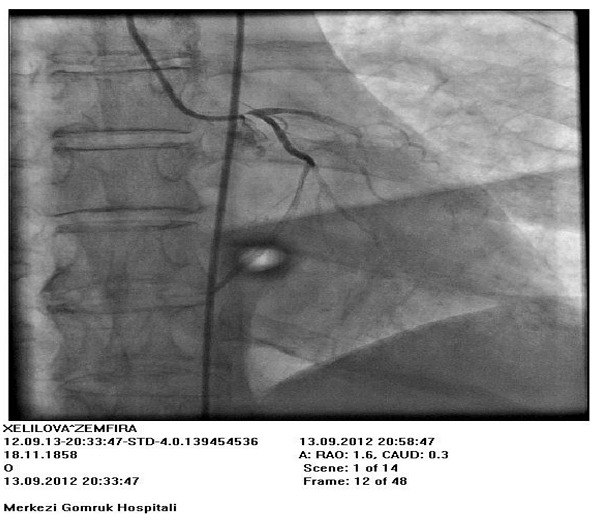

Фигуры